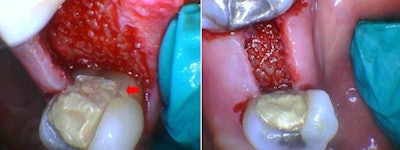

Next, the periodontal flap was raised using traditional periodontal instrumentation. Osseous tissue was ablated to establish the biologic width while exposing sufficient tooth structure coronal to the alveolus for proper restoration.

The spot size was switched to a smaller diameter for more precise control while ablating bone adjacent to the tooth structure. Note the good blood perfusion of the alveolar bone. The red arrow in figure 5 shows the bone level relative to a reference point near the cementoenamel junction after bone ablation before suturing. The flap is shown before approximation and suturing (figure 6).